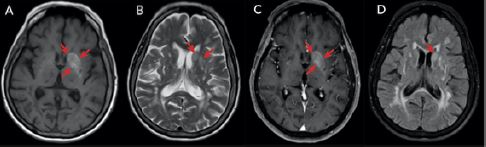

Se le tomó una resonancia magnética nuclear de cerebro simple y contrastada ( figura 2) que reportó un aumento de la señal en T1 hacia el núcleo caudado, el putamen y el globo pálido izquierdos; también con alta señal en T2 y FLAIR que no restringía en la difusión ni en el mapa. Adicionalmente, se observaron múltiples infartos lacunares crónicos de sustancia blanca y cerebelo izquierdo. Con los antecedentes patológicos, los hallazgos clínicos y este resultado, se hizo el diagnóstico de hemicorea inducida por HC-HN. Entonces, se le controló la glucemia con un esquema de insulina basal/bolo y se adicionó haloperidol para controlar los movimientos. Luego de 6 días de tratamiento se evidenció mejoría clínica y se indicó alta médica con seguimiento ambulatorio por parte del servicio de neurología.

En nuestra paciente del caso 2, la RMN mostró una hiperintensidad en T1 y en T2, en los núcleos lenticular, globo pálido y caudado del lado izquierdo e ipsilateral a la hemicorea de la paciente. Como se describió, lo más común es una afectación contralateral, por lo cual este hallazgo es claramente inusual en este síndrome. Se han descrito pocos casos similares a este, uno de ellos por Fong et al. ( 9), en el cual se evidenciaban lesiones en los ganglios basales bilaterales, pero con mayor compromiso radiológico en los ganglios ipsilaterales a la hemicorea de su paciente, contrario a lo observado en nuestro caso, en el cual las lesiones eran unilaterales (en los ganglios basales izquierdos). Ellos plantean dos posibles explicaciones: